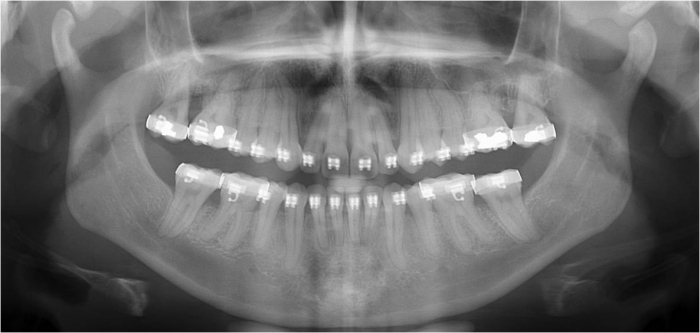

Raio x inicial